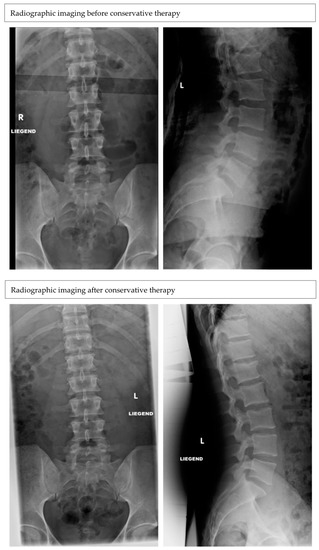

Radiographic Outcomes of Conservative and Operative Treatment in Isolated L1 Fractures

3. Results